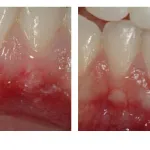

Recession around incisors

Following procedure to cover gingival recession